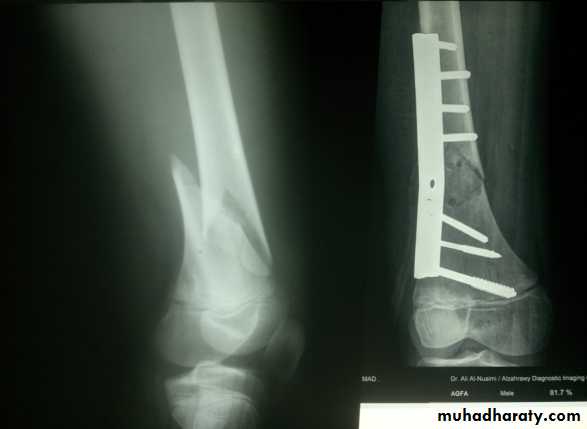

Supracondylar fractures of femur

In young adults after high energy injury.

In elderly osteoporotic after trivial injury.

Intercondylar extension may occur.

Supracondylar fracture with intercondylar extension

Supracondylar fracture femur

Treatment

Slightly displaced #s- skeletal traction through proximal tibia.If closed reduction fails- ORIF.

Locked intramedullary nail is the fixation of choice.